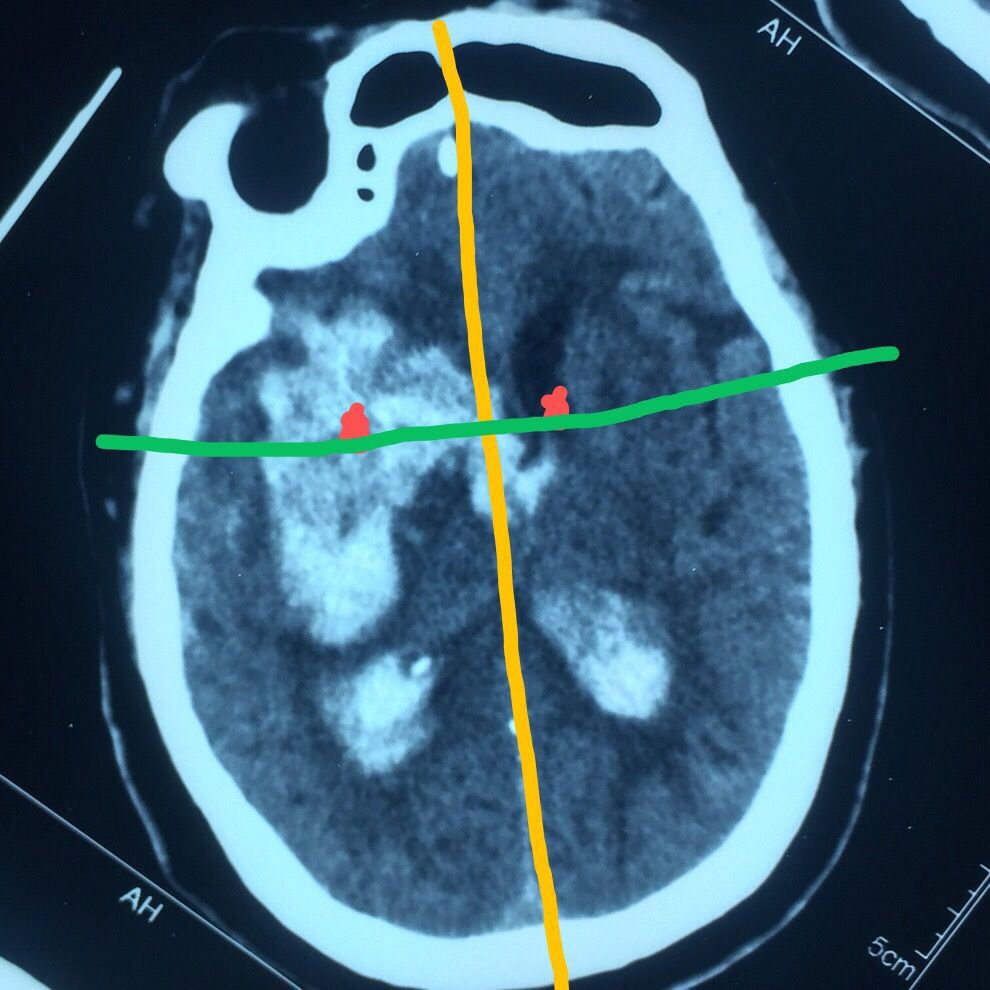

CT片见上图:

右侧基底节出血破入脑室脑积水

认真阅片可知,血肿最大层面就是脑室额角层面,EVD的靶点就是额角室间孔位置,我们把血肿靶点也定在这一层,右侧血肿内,右侧额角室间孔位置偏右,如图↑↑